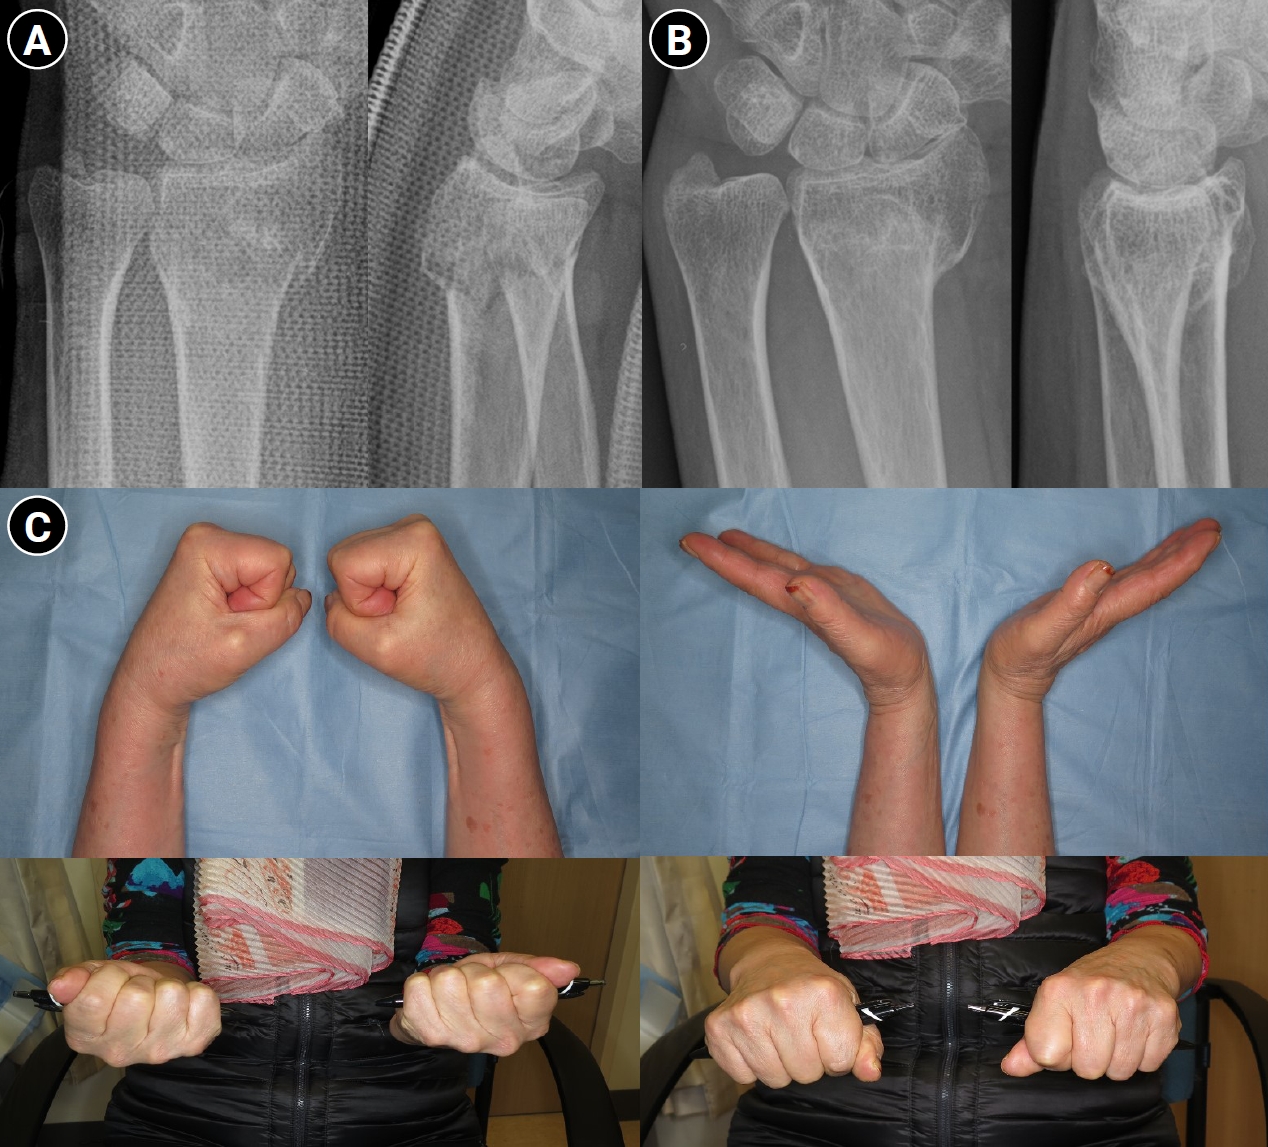

Elevation of the hand is essential to prevent swelling after injury. The use of a sling is not recommended because it positions the hand below the level of the heart; instead, the hand should always be kept above the elbow. Continuous finger motion is necessary. Importantly, finger motion must include full metacarpophalangeal (MCP) joint flexion and full interphalangeal (IP) joint extension rather than motion limited to the IP joints alone (Fig. 3). If active exercise alone is insufficient, assisted active exercise using the contralateral hand should be performed so that the patient can fully clench the fist and achieve full finger extension. Assisted exercises should apply sustained, gentle pressure rather than abrupt force to the joints. Additionally, during prolonged immobilization, contractures may develop in nonimmobilized joints such as the shoulder or elbow; therefore, these joints should be moved regularly from the time of injury [33].

Fig. 3.

Active finger range of motion exercise to prevent finger stiffness.

Fig. 3. Active finger range of motion exercise to prevent finger stiffness.